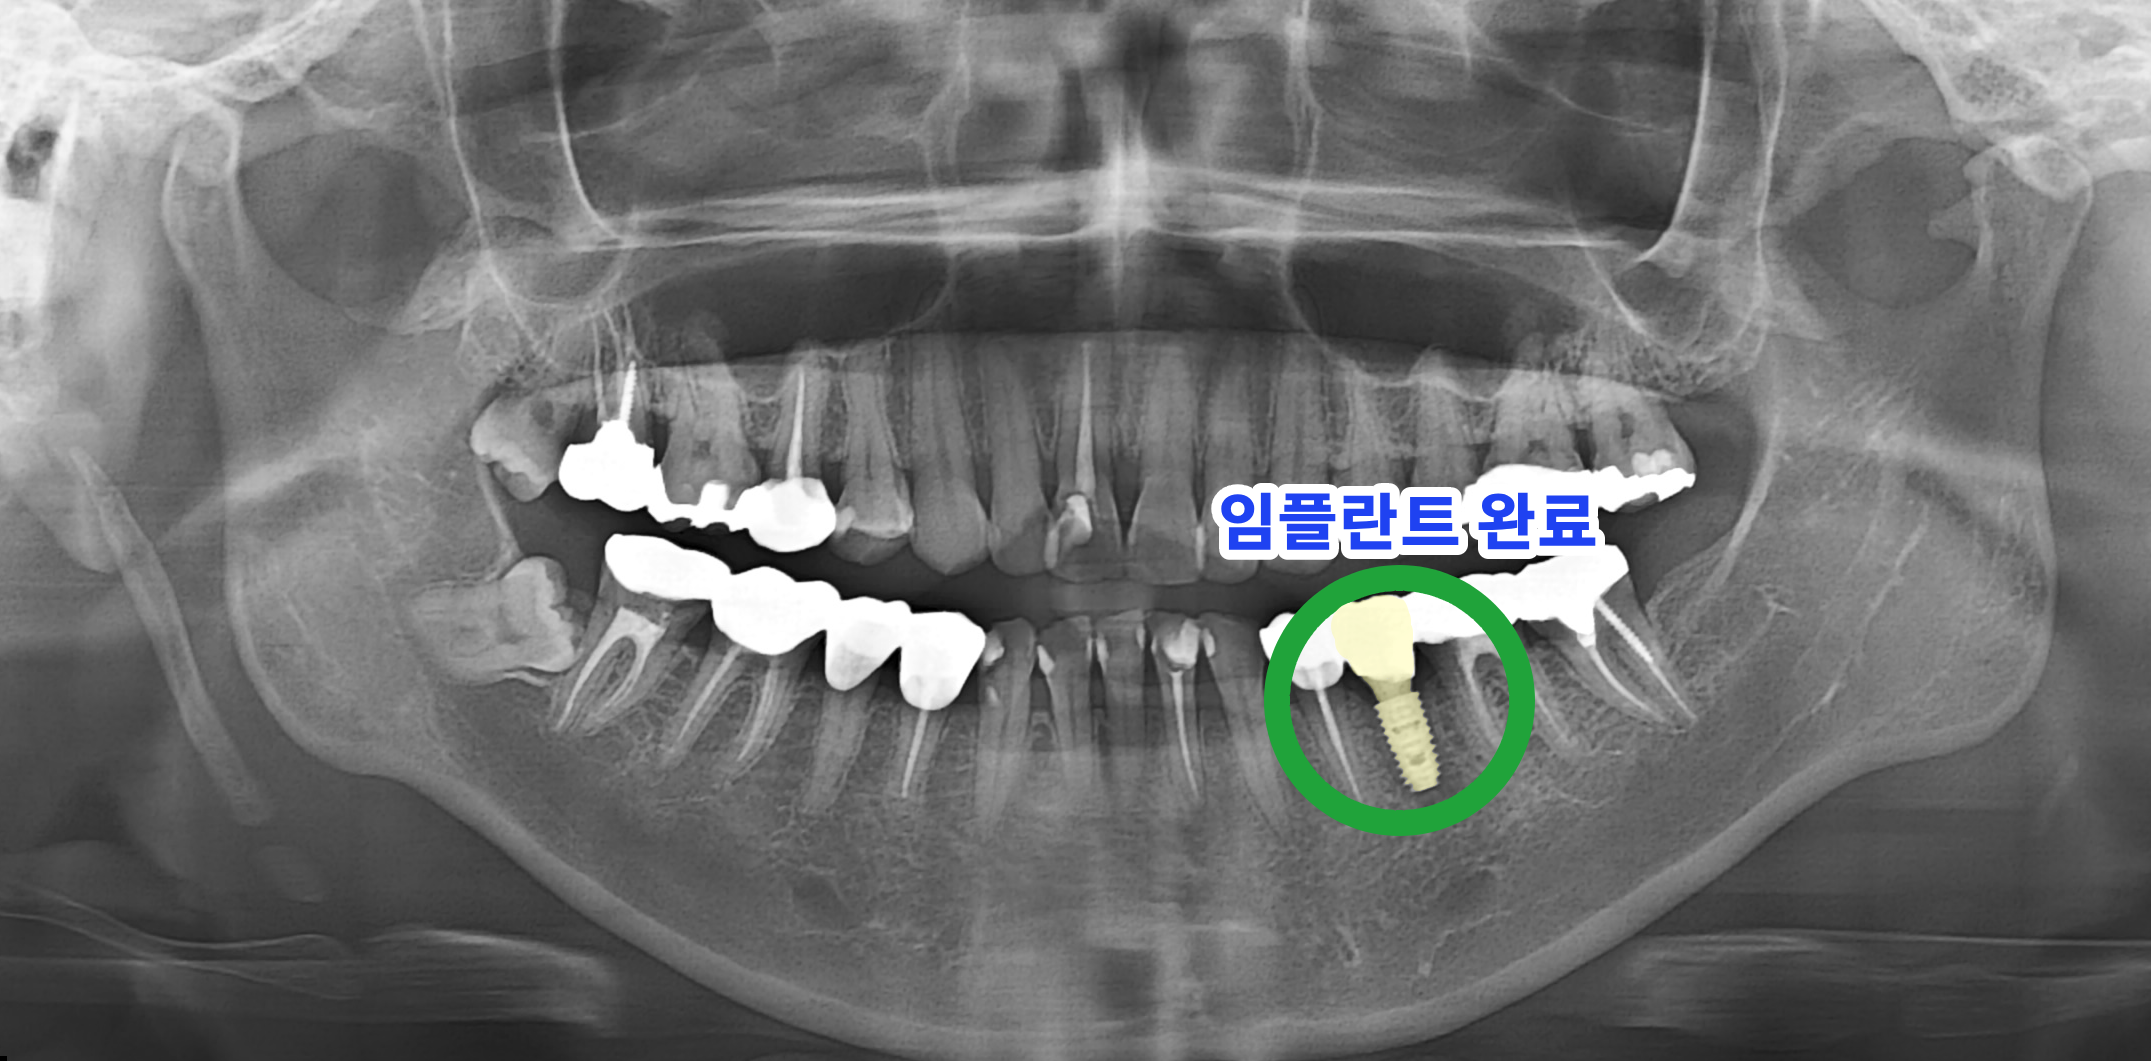

AFTER 치료 후 임플란트 식립 완료

치료 후 : 임플란트 보철물 결합 완료 (촬영일 : 2026.01.13)

치아가 상실된 35번 부위에 임플란트 픽스쳐를 식립하였습니다. 식립 시 부족한 잇몸뼈를 보강하여 임플란트의 안정성을 높이고자 인공 뼈이식술을 병행하였습니다.

임플란트와 잇몸뼈가 충분히 결합된 것을 확인한 후, 최종 보철물을 제작하여 연결함으로써 치료를 완료했습니다. 이를 통해 상실된 치아의 기능적, 심미적 회복을 도모하였습니다.